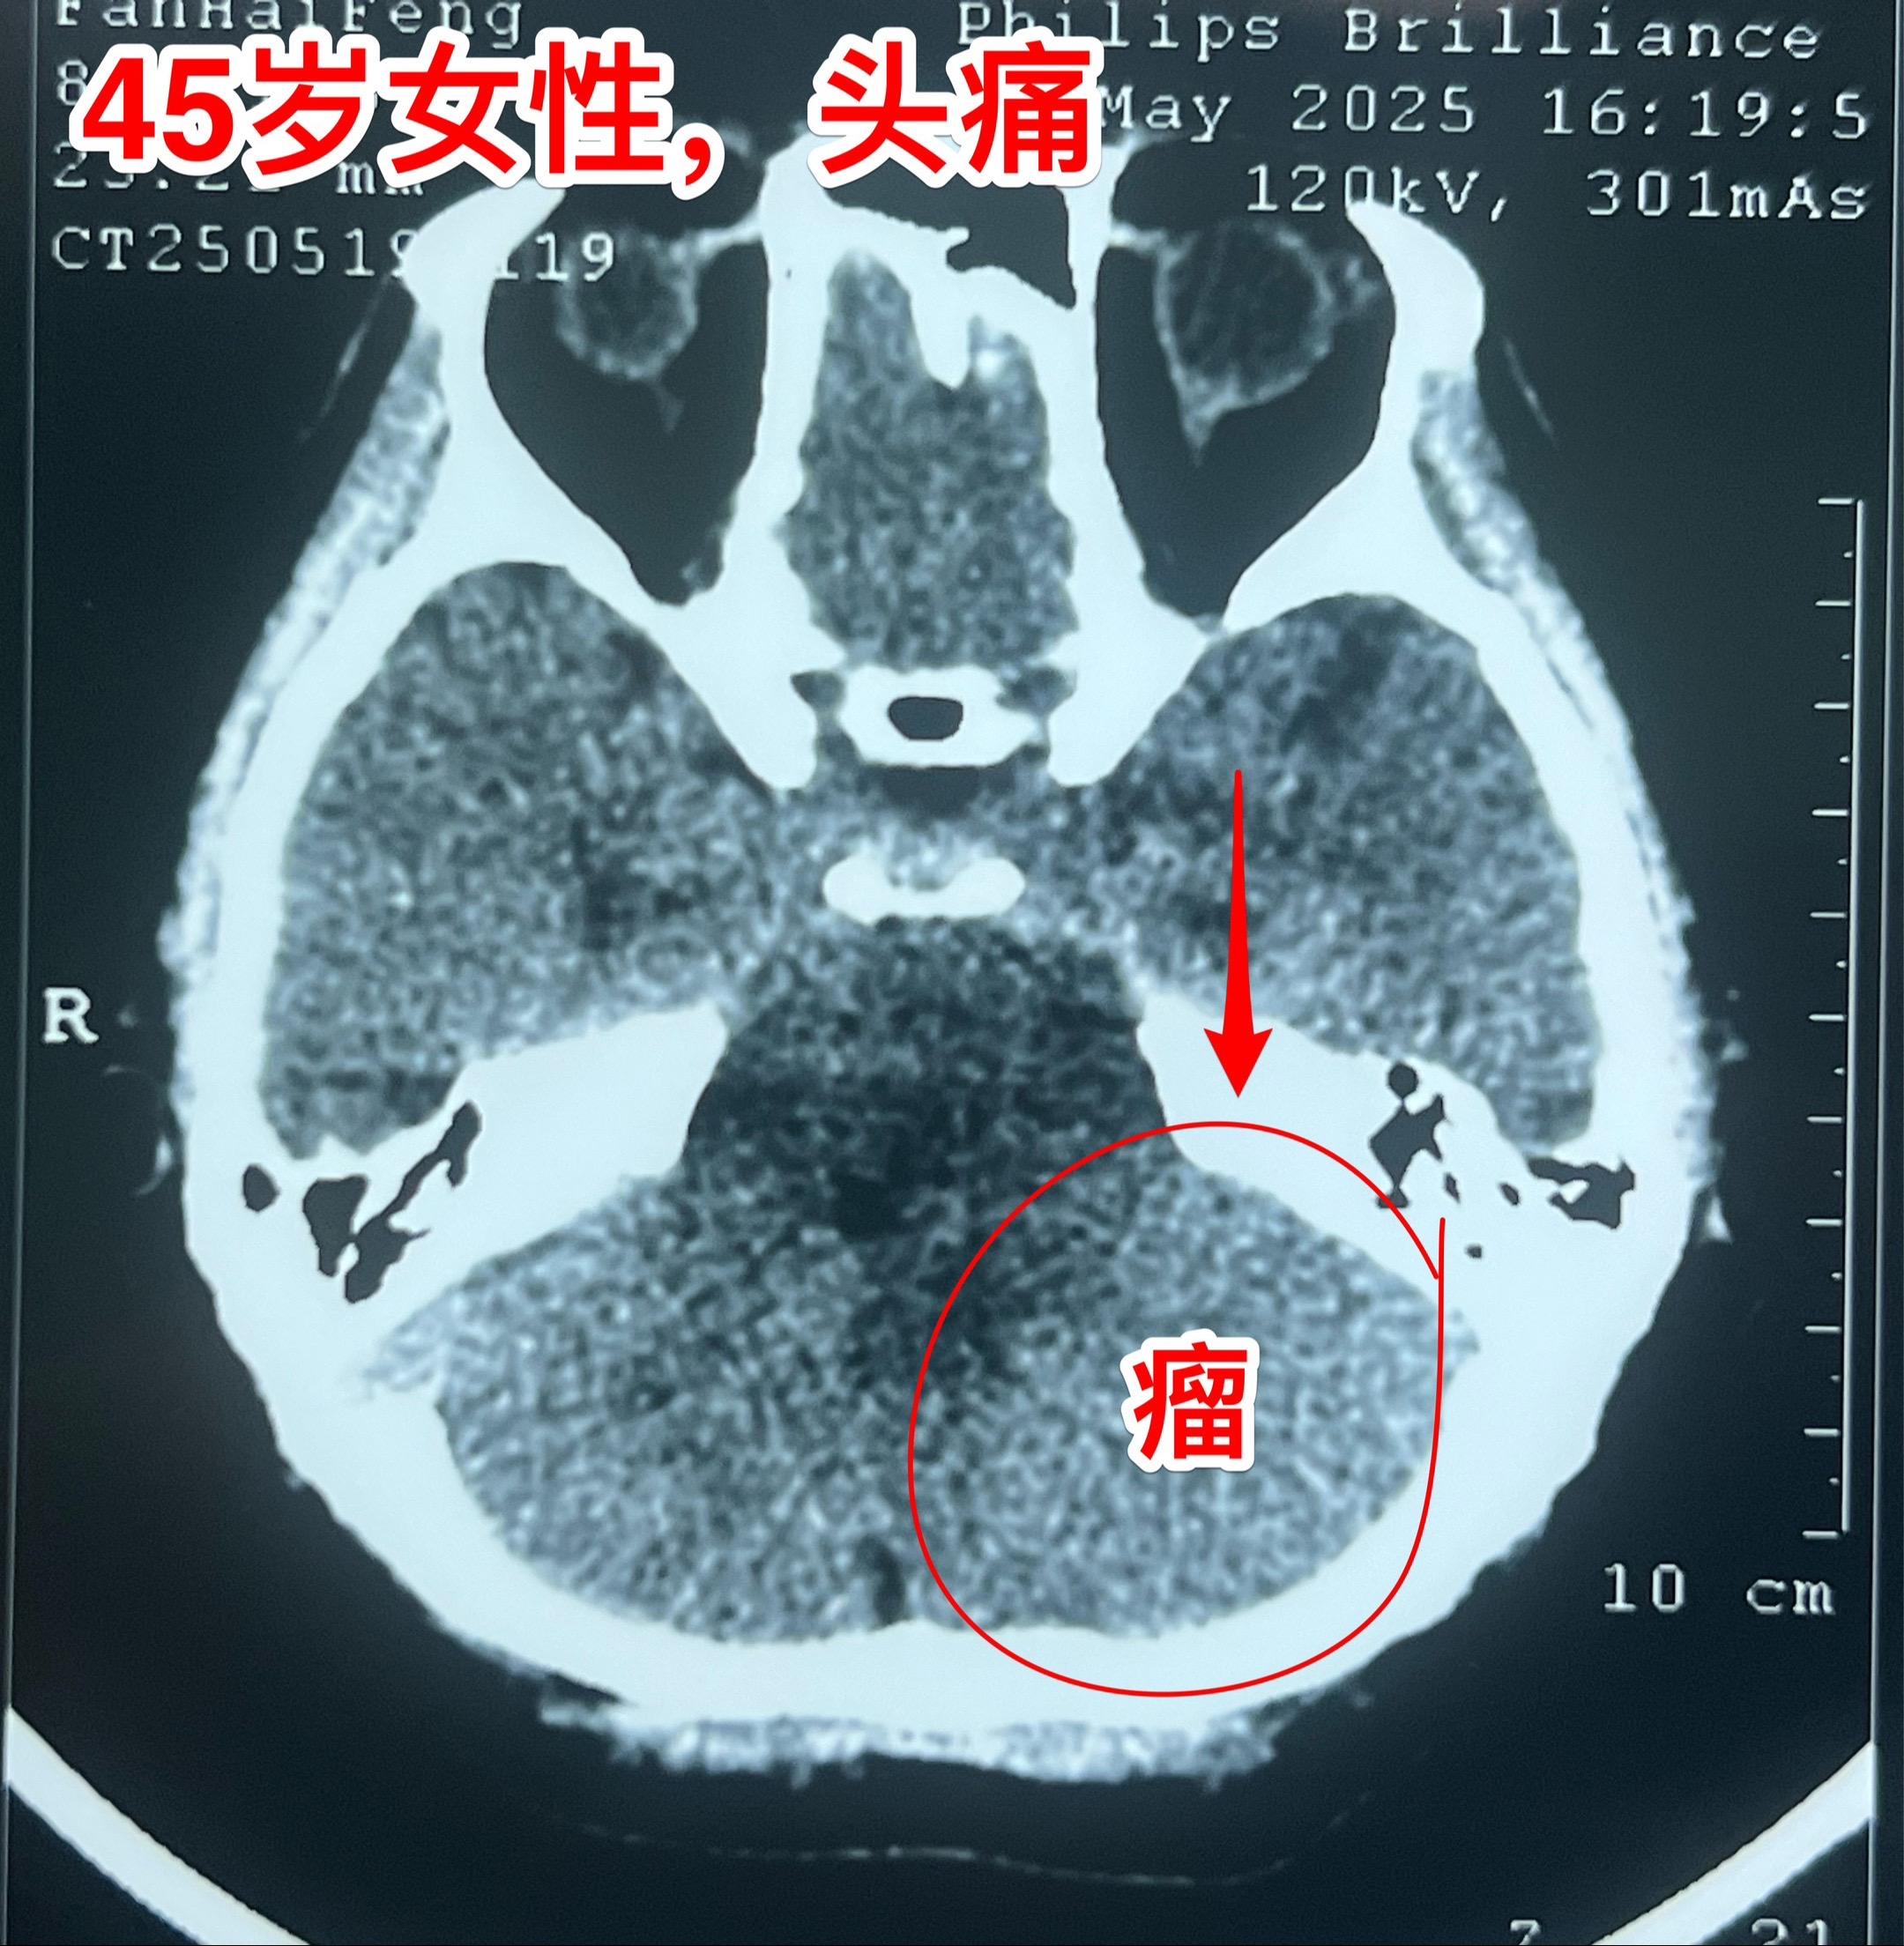

45岁女性因头痛发现脑膜瘤。45岁呼伦贝尔女性,在北京工作。头痛症状不剧烈,无呕吐。到医院就医,作头部CT检查发现可疑问题,再作磁共振检查发现左侧小脑表面有个巨大的脑膜瘤,伴有脑积水。 5月23日作了手术(只能是开颅手术)将脑膜瘤完全切除。 这样的脑膜瘤属于相对浅表位置的肿瘤,比颅咽管瘤手术要容易的多。脑膜瘤虽然是良性肿瘤,也有一定的复发率。